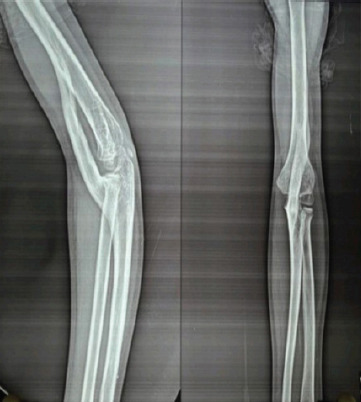

Introduction: Myositis ossificans traumatica (MOT) of the elbow is a rare entity in children. It is a self-localized tumor-like lesion of the elbow causing ankylosis due to humeroulnar bridging. It is a complication arising due to a muscle contusion injury.

Case report: We report a case of an 8-year-old female who presented with a 2-year history of a fixed elbow and a palpable bony mass. The examination confirmed a confined bony mass on the anterior aspect and ankylosis of her left elbow. On confirmation of the diagnosis, an en bloc excision was performed. Follow-up every 2 weeks for the first 3 months, then once a month for the next 6 months, and finally once every 6 months for the next 4 years. The affected limb functioned well, with no sign of recurrence.

Conclusion: MOTs of the elbow in children are a rarity, and excision of the lesion without delay is an effective management strategy for a satisfactory outcome.